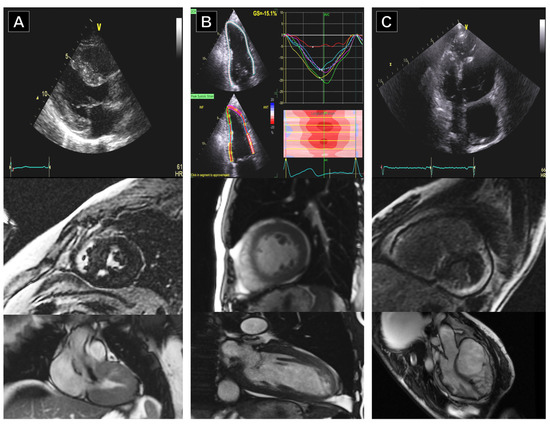

5.1. Dilated Cardiomyopathy (DCM)

5.2. Hypertrophic Cardiomyopathy (HCM)

5.3. Arrhythmogenic Cardiomyopathy (ACM)

5.4. Left Ventricular Non-Compaction (LVNC)